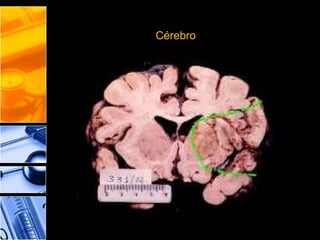

Pode-se formar em qualquer órgão, porém é mais comum nos rins, baço,

coração e cérebro. (No tecido nervoso devido a sua riqueza em lipídios e

água, a zona de necrose amolece rapidamente, tonando-se semilíquida).

Cérebro